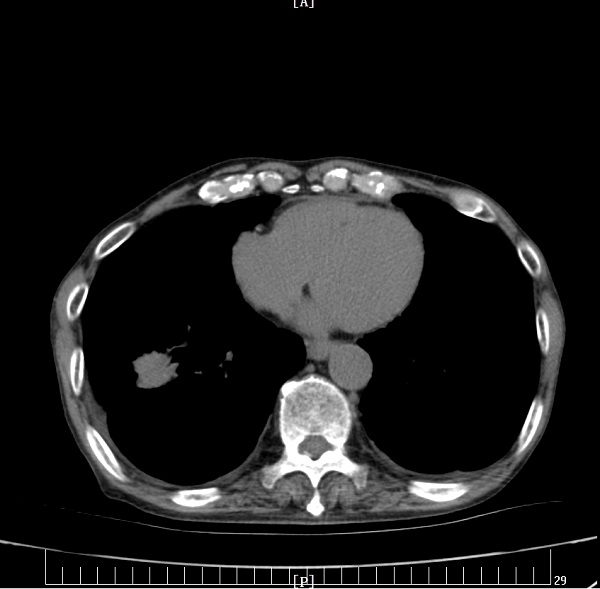

充分研究病情后,刘娟妮主任团队积极与家属沟通,对症治疗的同时,在CT引导下行经皮肺穿刺活检术,术后病理提示:中分化腺癌,基因检测结果提示:EGFR Exon19突变。明确诊断后,刘娟妮主任团队一边安慰患者及家属的情绪,一边对患者的全身状况及疾病进行了充分的评估,邀请相关科室会诊,经MDT讨论并结合患者目前症状、基因检测结果分析及国内外最新指南推荐,制定了个性化的治疗方案,给予口服三代靶向药控制肿瘤。治疗1个月后,复查头颅MRI及胸部CT,结果显示患者肺原发肿瘤、脑多发转移瘤较前均缩小、部分消失。

治疗前

治疗后